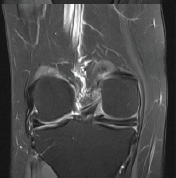

A 44-year-old surgeon presented to us with complaints of right knee pain and instability. He had an anteromedial blow to his right knee after slipping from an elevated platform while he was operating, 4 weeks back. He had no medical comorbidities and was unable to carry out his activities of daily life. On physical examination, the right knee exhibited a positive Grade 2 posterior drawer test along with a dial test showing external rotation asymmetry at 30° as well as at 90° (Fig. 1). There was Grade 3 lateral opening on varus stress and the common peroneal nerve (CPN) examination was unremarkable. Bilateral varus stress radiographs of the knee showed a side-to-side difference of more than 4 mm (Fig. 1). A bilateral lower limb scanogram showed no alignment issues, whereas the magnetic resonance imaging showed a lateral collateral ligament (LCL) tear at the fibular attachment with 1.4 cm retraction and popliteal tendon disruption at the myotendinous junction. PCL showed a partial to full-thickness tear in the midsubstance (Fig. 2). After a thorough evaluation of the physical and radiographic examination, and considering the age and active lifestyle of the patient, we decided on an Arciero-based PLC ligament reconstruction using tibialis anterior allograft. The surgery was performed according to Arciero’s “3-window technique” with a few modifications. A hockey stick incision was made, extending from the distal femoral shaft along the iliotibial band (ITB) proximally, and continuing distally between Gerdy’s tubercle and the fibular head. The third window was created first, inferior to the biceps femoris, where the CPN was identified, protected and exposed distally up to the fibula head. The second window was made between the anterior border of the biceps femoris and the posterior border of the ITB, for future passage of the graft. The first window was then developed by splitting the ITB along its midline and centered over the lateral femoral condyle (Video 1).